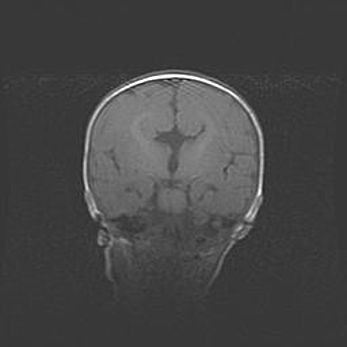

Открытая гидроцефалия.

Возраст: 6 месяцев 15 дней

Вес: 6200 г

Пол: женский

Окружность головы: 41 см

Срок гестации: 38 недель

Гидроцефалия головного мозга у новорожденных – это скопление избыточного количества цереброспинальной жидкости в головном мозге. Ее избыточное скопление в мозге приводит к патологическому расширению желудочков мозга (четырех полостей, расположенных в глубине белого вещества мозга, заполненных цереброспинальной жидкостью и связанных узкими проходами).

Открытый тип гидроцефалии (сообщающаяся) наблюдается тогда, когда нарушен механизм всасывания ликвора в системный кровоток. При этом типе причиной заболевания чаще всего является перенесенные ранее инфекции (например: менингит),  либо же наличие крови в субарахноидальном пространстве.